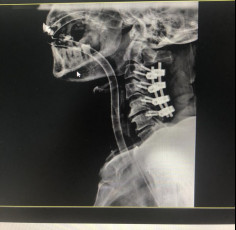

(術(shù)后拍片)

治療效果顯著康復(fù)出院

術(shù)后的康復(fù)漫長卻成效顯著,好消息一個(gè)個(gè)地傳來。在醫(yī)護(hù)人員的悉心治療下,病人癱瘓的右手患肢功能開始恢復(fù),已經(jīng)可以自主用勺子吃飯;2020年12月29日,手術(shù)后第25天,張阿伯可在腰帶保護(hù)下下地;2021年1月11日,張阿伯可以在家人的幫助下緩慢行走;術(shù)后44天,經(jīng)過近1個(gè)半月的康復(fù)治療,張阿伯已經(jīng)可以自行下地走路;2021年3月5日,張阿伯終于出院了。從瀕臨癱瘓困境中擺脫出來后,讓這個(gè)和諧幸福的家庭充滿了感激之情。

今年5月,張阿伯出院近2月后,大部分生活已經(jīng)可以自理。戈主任為張阿伯做了復(fù)查診治,結(jié)果顯示他的頸椎固定可靠,復(fù)位良好,病體正在朝理想的康復(fù)方向發(fā)展。